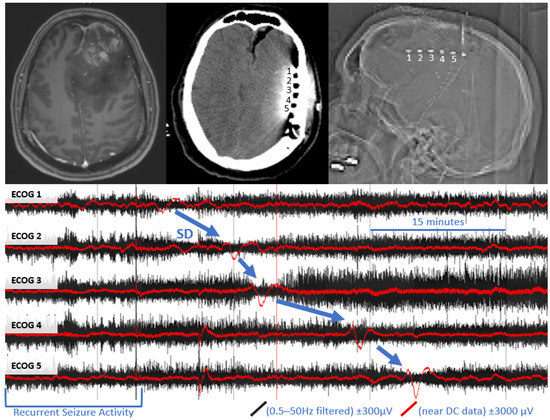

| Patient 3 | Headaches, blurred vision, extremity weakness, seizures, incontinence | Glioblastoma WHO Grade IV IDH1 Wild Type MGMT Promotor Hypermethylated | Left Frontal Lobe | 11 cm | Subtotal Resection | Y | Keppraa Dexamethasone |